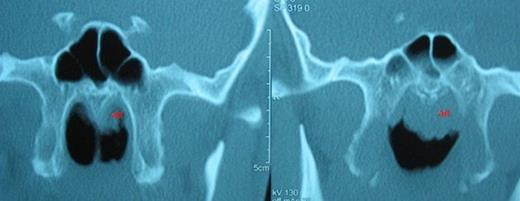

Asymmetric adenoid hypertrophy, more prominent on the left side. ad: adenoid hypertrophy

The patient underwent endonasal endoscopic surgery with the diagnosis of rhinolithiasis. The rhinolith was successfully removed with minimal possible injury to surrounding nasal mucosa. The nasal cavity was irrigated with saline. After removal of the rhinolith, adenoid hypertrophy was prominent on the left side (Figure 3). Adenoidectomy was subsequently performed and postoperative histopathologic examination revealed lymphoid hyperplasia and chronic inflammatory cell infiltration without any malignant transformation.